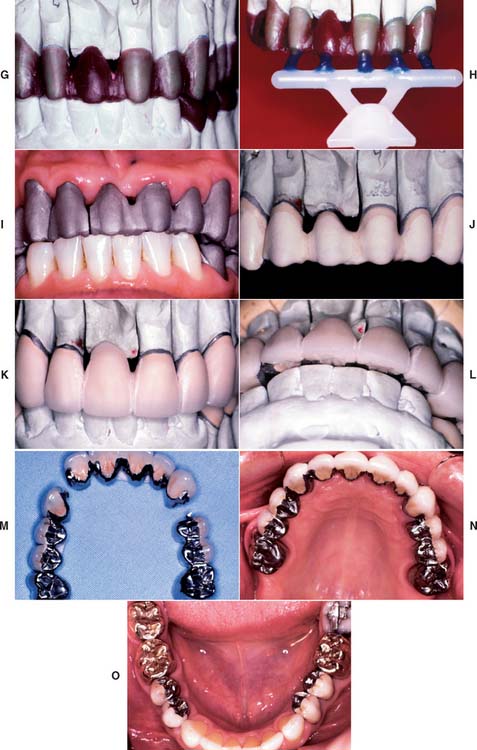

Fig. 32-29 Repair of a fractured metal-ceramic pontic. A, Pretreatment appearance. B, The ceramic veneer is removed with diamond rotary instruments. C, Appearance after porcelain removal. D, Special impression tray. E, Pinholes are placed in the substructure. F, Cast of the substructure. G and H, Waxed overlay. Note the plastic pins used (H). I, Cast overlay. J, Facial aspect. K, Proximal aspect. L, Facial aspect after the porcelain application. M, Lingual aspect after firing (cast relieved). N, Appearance after cementation. O and P, The finished repair.

(Courtesy of Dr. A. G. Gegauff.)